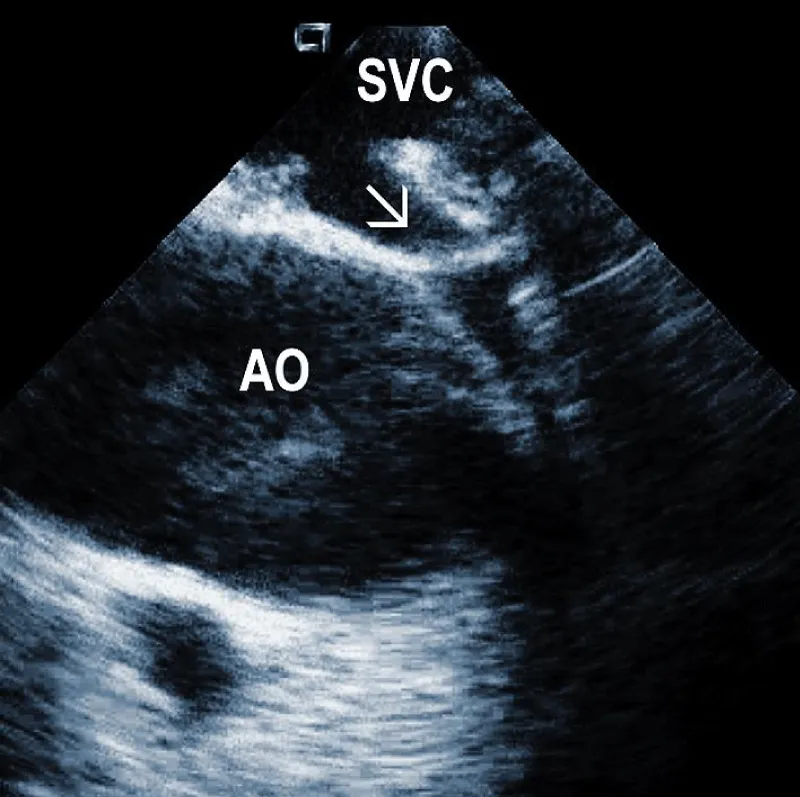

Residuals after TLE: Residual fibrotic tissue after TLE, called ghosts, has been described as a new phenomenon in cardiology (Figure 4). The presence of ghosts was first described by Rizzello, et al. using ICE [22]. Caiati, et al. studied a cohort of 40 patients using ICE before and after TLE to document the relationship between thrombotic or fibrotic reactions to the lead and with subsequent occurrence of ghosts [23]. ICE could identify thickened lead (thickness ≥ 1 mm than the vendor declared thickness in at least one lead) and fibrotic attachment to the cardiac wall in a substantial number of subjects. Thickening was noted in 25/40 patients (62%) overall, involving the atrial (2 patients (5%)) or the ventricular (9 patients (22.5%)) or both leads (14 patients (35%)). The fibrotic attachment was observed in 12/40 patients (30%). Both thickening and fibrotic attachments were significantly associated with subsequent ghosts (p < 0.001 and p = 0.002, respectively), but lead thickening had a higher prediction power. Narducci, et al. demonstrated that the presence of ghosts could be associated with a worse prognosis in device-related infective endocarditis [24]. Analyzing 217 TLE cases, the authors identified ghosts in 30 (14%) patients after TLE. In their study, endocarditis was one of the independent predictors of the presence of ghosts. Poterala, et al. detected ghosts after TLE in 19% of cases [25]. These residual fibrotic tissues were most often located along the originally implanted lead’s route. The local infection and infective endocarditis were associated with a larger number of ghosts after the removal procedure (p = 0.006). Besides frequent association with infection, detection of ghosts after TLE is also important for other reasons. Otherwise, they can be mistakenly interpreted in the echocardiographic examination as new pathological structures of unknown origin. In such a situation, the patient can be subject to unnecessary anticoagulant therapy, invasive diagnostic procedures, and/or cardiac surgery. Given the potential risks of ghosts, their presence should probably be noted on post-extraction imaging and might warrant closer post-extraction follow-up [4].

Figure 4: Ghosts within the superior vena cava (SVC) after removal of the ICD leads marked by arrows. AO: Aorta.